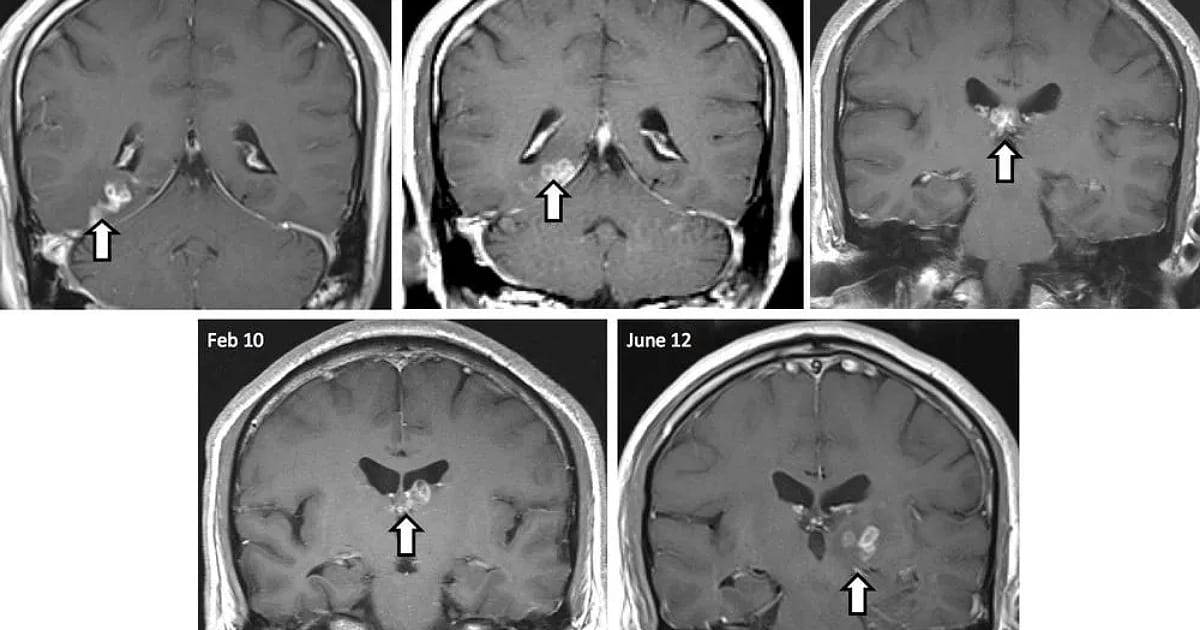

ವೈದ್ಯರು ವೈದ್ಯಕೀಯ ಪರೀಕ್ಷೆಗಳನ್ನು ನಡೆಸಿದಾಗ ಝುಗೆ ಟೈನಿಯಾಸಿಸ್ ರೋಗ ಲಕ್ಷಣಗಳನ್ನು ತಿಳಿಸಿದ್ದಾರೆ. MRI ಸ್ಕ್ಯಾನ್ನಲ್ಲಿ ಅವರ ಮೆದುಳು, ಎದೆ ಮತ್ತು ಶ್ವಾಸಕೋಶಗಳು ಒಳಗೊಂಡಂತೆ ಅವರ ದೇಹದಲ್ಲಿ 700 ಕ್ಕೂ ಹೆಚ್ಚು ಟೇಪ್ ಹುಳುಗಳು (Tape worm)ಕಂಡುಬಂದಿದೆ ಎನ್ನಲಾಗಿದೆ. ಟೇಪ್ ವರ್ಮ್ ಮೊಟ್ಟೆಗಳನ್ನು ಒಳಗೊಂಡಿರುವ ಬೇಯಿಸದ ಇಲ್ಲವೇ w ಹಂದಿಮಾಂಸವನ್ನು ಸೇವಿಸಿದ ಬಳಿಕ ಝು ಅವರ ದೇಹದಲ್ಲಿ ಟೇಪ್ ವರ್ಮ್ಗಳು ಕಂಡುಬಂದಿವೆ.